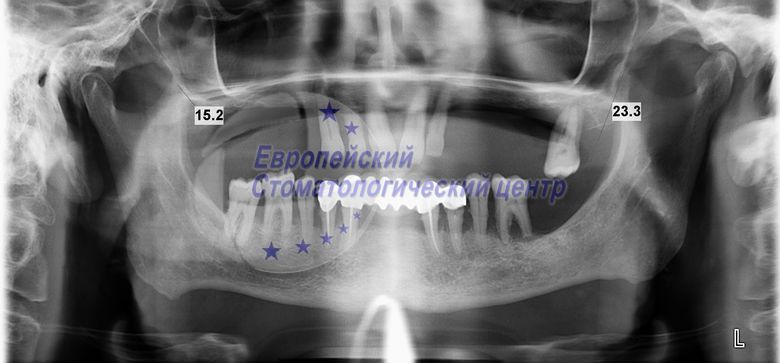

OPG before surgery